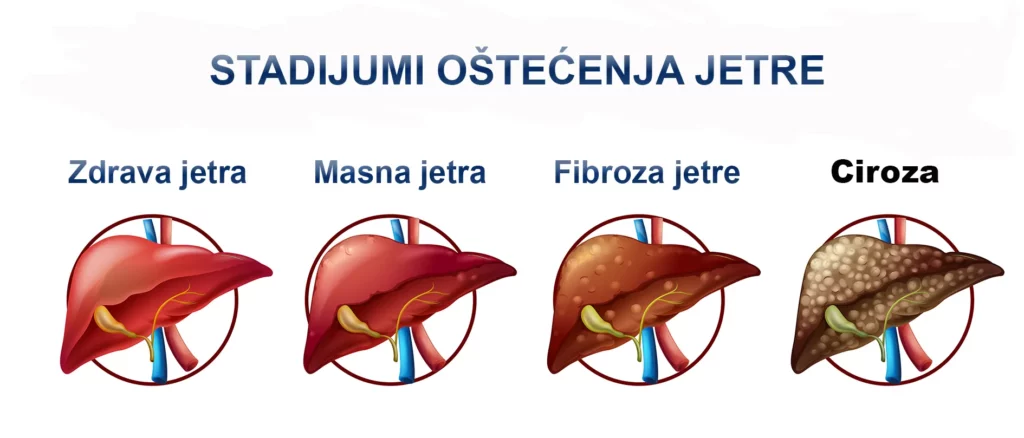

Kao što smo pretodno rekli prvi stadijum bolesti jetre je upala koja nastaje kao posledica dejstva različitih toksina, virusne infekcije i previše masnoće što utiče na uvećanje jetre. Većina ljudi oseća tup, pulsirajući bol u gornjem delu stomaka, na desnoj strani ispod rebara. Ponekad taj bol može da bude i probadajući što izaziva gubitak daha. Kod nekih osoba bol se širi na leđa, ispod lopatice. Uznapredovala masna jetra vodi ka fibrozi, stadijumu u kome se na mestu zdravih ćelija jetre (hepatocita) nalazi fibrozno tkivo koje ne može da učestvuje u detoksikaciji organizma. U sledećem stadijumu rast fibroznog tkiva sve više uništava ćelije jetre. Fibroza zatim prelazi u cirozu koju odlikuje odumiranje velikog broja hepatocita i može uznapredovati do raka jetre.